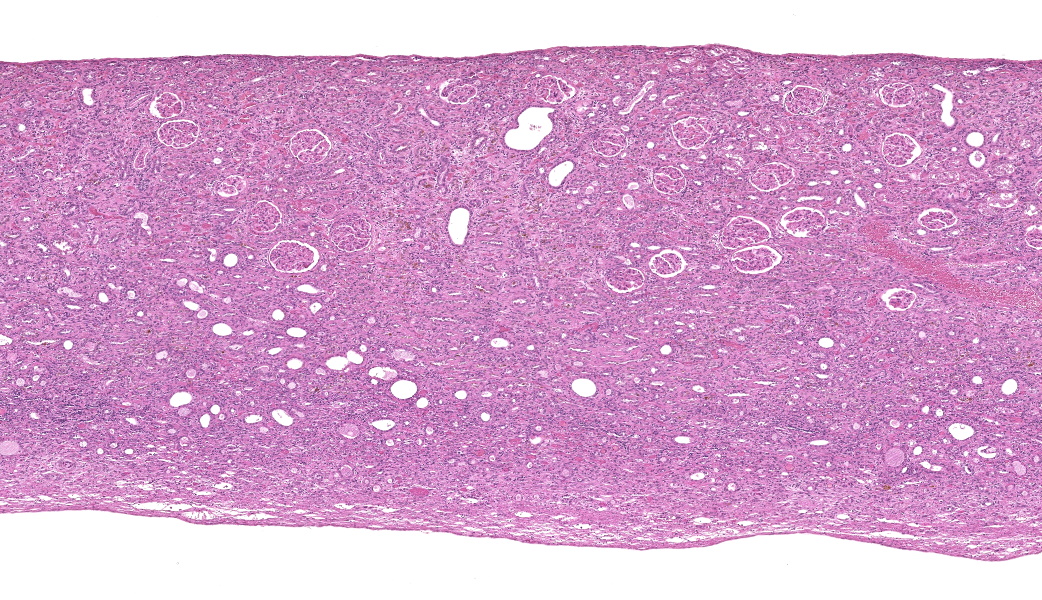

Kidney: There is severe dilation of the renal pelvis with marked thinning of the renal medulla and cortex.

Kidney: Hydronephrosis, severe.

- Kidney: Hydronephrosis, chronic, diffuse, severe.

One of the most instructive aspects of this case was the hydronephrosis, which was beautifully captured on the H&E slide. Dr. Alves emphasized not to overlook this lesion: the upstream consequences of urinary outflow obstruction (pelvic dilation, cortical and medullary thinning, tubular atrophy) were classic! The obstruction in this rat was likely caused by the combination of the tumor?s size and its pronounced desmoplastic response, which occluded the bladder outlet.